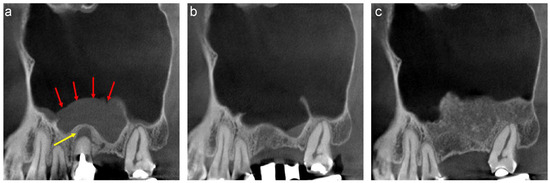

A 58-year-old male was referred to our clinic by his dentist for implant treatment of the right maxilla in 2018. Well-defined, faintly radiopaque antral lesions were observed on the mesiodistal section of the CT image acquired at the first visit. Moreover, marked alveolar bone resorption was observed in the regions surrounding 16, 15, and 14 (Figure 1a, red arrows). The requirement for extraction of these teeth and sinus floor elevation for implant treatment was explained to the patient. The well-defined, faintly radiopaque antral lesions were found to have disappeared on the CT image acquired 3 months after the extractions (Figure 1b); thus, sinus floor elevation was performed using β-TCP granules (Osferion; Olympus Terumo Biomaterials, Tokyo, Japan) alone and 17 was extracted simultaneously at our clinic. CT images acquired 6 months postoperatively revealed a radiopaque area at the site that underwent sinus floor elevation. Swelling of the sinus membrane was not observed (Figure 1c).

Figure 1.

The mesiodistal section of CT images of the right maxillary sinus. (a) Antral, well-defined, faintly radiopaque lesions (red arrows) and marked alveolar bone resorption are observed near 16, 15, and 14. (b) The well-defined, faintly radiopaque antral lesions disappeared 3 months after extraction. (c) A radiopaque area is observed at the sinus floor elevation without swelling of the sinus membrane six months postoperatively.